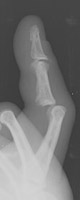

- Click on the image for a larger versionALateral radiograph of the hand. This demonstrates an angulated fracture of the fourth proximal phalanx.